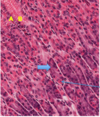

sinusoidal capillaries

what we call sinusoidal capillaries that are found at either side of hepatocytes (2).